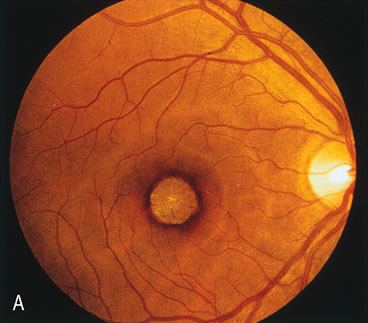

In retinitis pigmentosa (RP), the pigment abnormalities of atrophy, migration, and clumping are made apparent by transmitted hyperfluorescence and blocked hypofluorescence (Fig. 1A). Patients who have very minimal pigmentary alterations (pauci pigmentary RP) or no pigment abnormalities (RP sine pigmento) may show the abnormalities on fluorescien angiography (FA). It is uncommon to see choriocapillaris atrophy except in the late stages. This finding corresponds to the histopathology, which shows that the earliest abnormalities are in the photoreceptors and that the choroid is normal.1